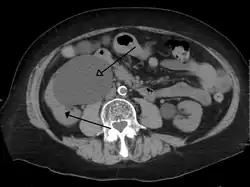

CT scan of bilateral hydronephrosis due to a bladder cancer